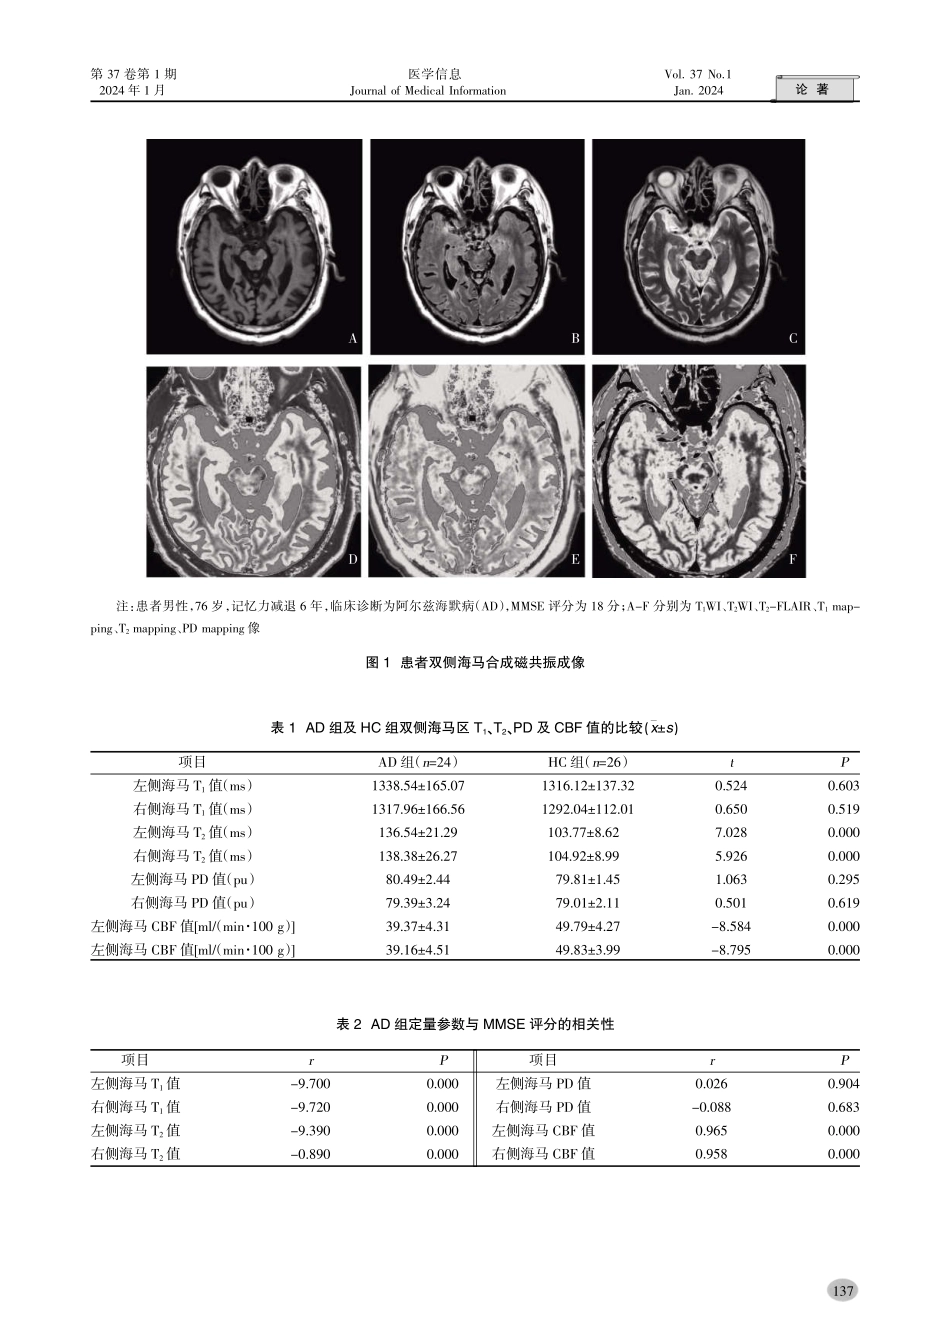

论著第37卷第1期医学信息Vol.37No.12024年1月JournalofMedicalInformationJan.2024作者简介:童玉洁(1994.10-),女,河南信阳人,硕士研究生,主要从事医学影像学与核医学研究通讯作者:翟冬枝(1964.10-),女,河南郑州人,博士,主任医师,主要从事医学影像学与核医学研究合成MRI联合3D-ASL在阿尔兹海默病诊断中的价值童玉洁袁翟冬枝袁李真真袁刘华渊郑州大学第二附属医院医学影像科袁河南郑州450000冤摘要院目的探讨合成磁共振成像渊SynMRI冤联合三维动脉自旋标记成像渊3D-ASL冤序列在AD中双侧海马定量值的变化袁研究二者联合对阿尔兹海默病渊AD冤早期诊断的价值遥方法收集2022年1月-6月在郑州大学第二附属医院就诊经临床诊断为AD患者24例作为阿尔兹海默病组渊AD组冤袁同时按照年龄尧性别和教育程度相匹配的条件下从健康体检者中纳入26例作为本次实验的健康对照组渊HC组冤遥所有受试者均在3.0TGEMRI扫描仪上进行MAGiC序列和3D-ASL序列扫描袁选取双测海马作为感兴趣区渊ROI冤袁并分别测量其感兴趣区的T1尧T2尧PD及CBF值袁并且所有受试者均获得简易精神状态检查渊MMSE冤评分遥记录AD组与HC组双侧海马值袁并与MMSE评分之间进行Pearson相关分析遥结果AD组患者与HC组之间双侧海马的T1值及PD值比较袁差异无统计学意义渊跃0.05冤曰AD组的T2值高于HC组袁而CBF值低于HC组渊约0.05冤曰AD患者随着MMSE评分的降低袁双侧海马的T1值尧T2值升高尧CBF值降低渊约0.05冤遥结论合成MRI联合3D-ASL对AD患者双侧海马区域具有很好的定量价值袁可以对AD进行早期诊断遥关键词院阿尔兹海默病曰合成MRI曰3D-ASL曰弛豫值曰脑血流量中图分类号院R445文献标识码院ADOI院10.3969/j.issn.1006-1959.2024.01.023文章编号院1006-1959渊2024冤01-0135-05ValueofSyntheticMRICombinedwith3D-ASLintheDiagnosisofAlzheimer'sDiseaseTONGYu-jie,ZHAIDong-zhi,LIZhen-zhen,LIUHua(DepartmentofRadiology,theSecondAffiliatedHospitalofZhengzhouUniversity,Zhengzhou450000,Henan,China)Abstract:ObjectiveToinvestigatethechangesofquantitativevaluesofbilateralhippocampusinADbysyntheticmagneticresonanceimaging(SynMRI)combinedwiththree-dimensionalarterialspinlabeling(3D-ASL)sequence,andtostudythevalueofthecombinationofthetwointheearlydiagnosisofAlzheimer'sdisease(AD).MethodsAtotalof24patientswithAlzheimer'sdiseasediagnosedclinicallyintheSecondAffiliate...